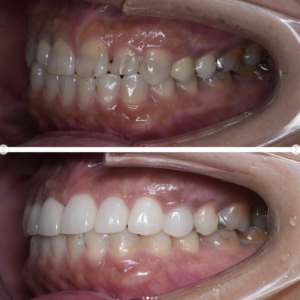

「ずっと放置してしまっていた。今回はちゃんとしっかり治したい」ということで、強い意志をもって来院してくださった患者様の症例です。

インプラント治療、セラミック治療、歯周病治療により、審美性と機能、咬みあわせの再建を行いました。

患者様は咬みあわせの確立により、食事もしやすく、普段の顎関節の状況も良くなり、機能の回復にも満足してくださり、また審美性も喜んでくださいました。

放置期間が長くだいぶ骨が溶けてしまっていたので、前歯部のインプラントは骨の再生療法などが必要だったりしましたが、患者様が治療への前向きな姿勢をだしてくださっていましたので期間も最短で終わりました。

一度放置してしまうと、億劫になってしまってなかなか行動に移すのは難しいと思いますが、少しでも早く治してあげた方が毎日の食事も楽になりますし、お顔の見栄えもお顔の骨格の歪みも改善します。